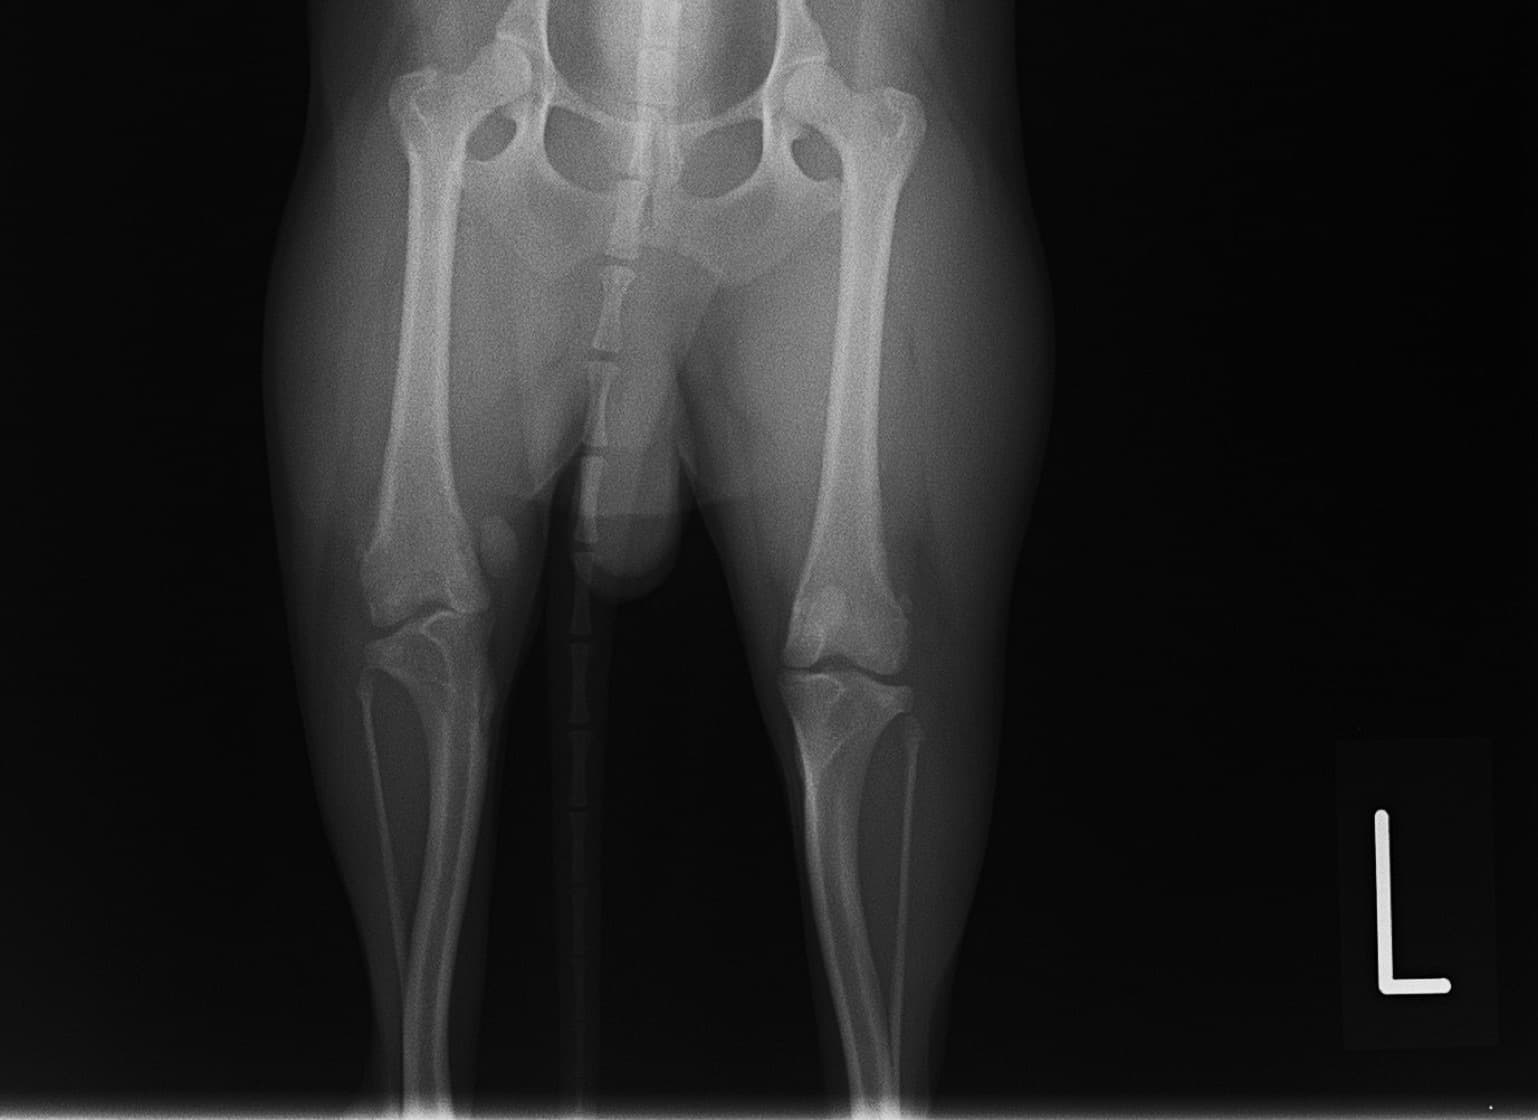

■ 症例24 キャバリア 7か月

左右膝蓋骨内方脱臼(左:グレードⅣ 右:グレードⅢ)

以前から左右後肢の跛行が認められ、整形外科学的検査・レントゲン検査により左右の膝蓋骨脱臼が認められた。症状が重度である左膝の膝蓋骨脱臼整復術を行った。外科手技は縫工筋及び内側広筋の解放、脛骨粗面の外側転位、滑車ブロック形造溝術、内外側関節方の縫縮を実施した。術後一か月時点で、左の膝蓋骨は安定しており経過は良好である。

本症例は成長期における重度の膝蓋骨脱臼であり、術後の再発の可能性もあるため、経過をしっかりと観察していく必要がある。また、今回手術を実施していない右膝に関しても経過を観察し、手術を検討していくこととする。